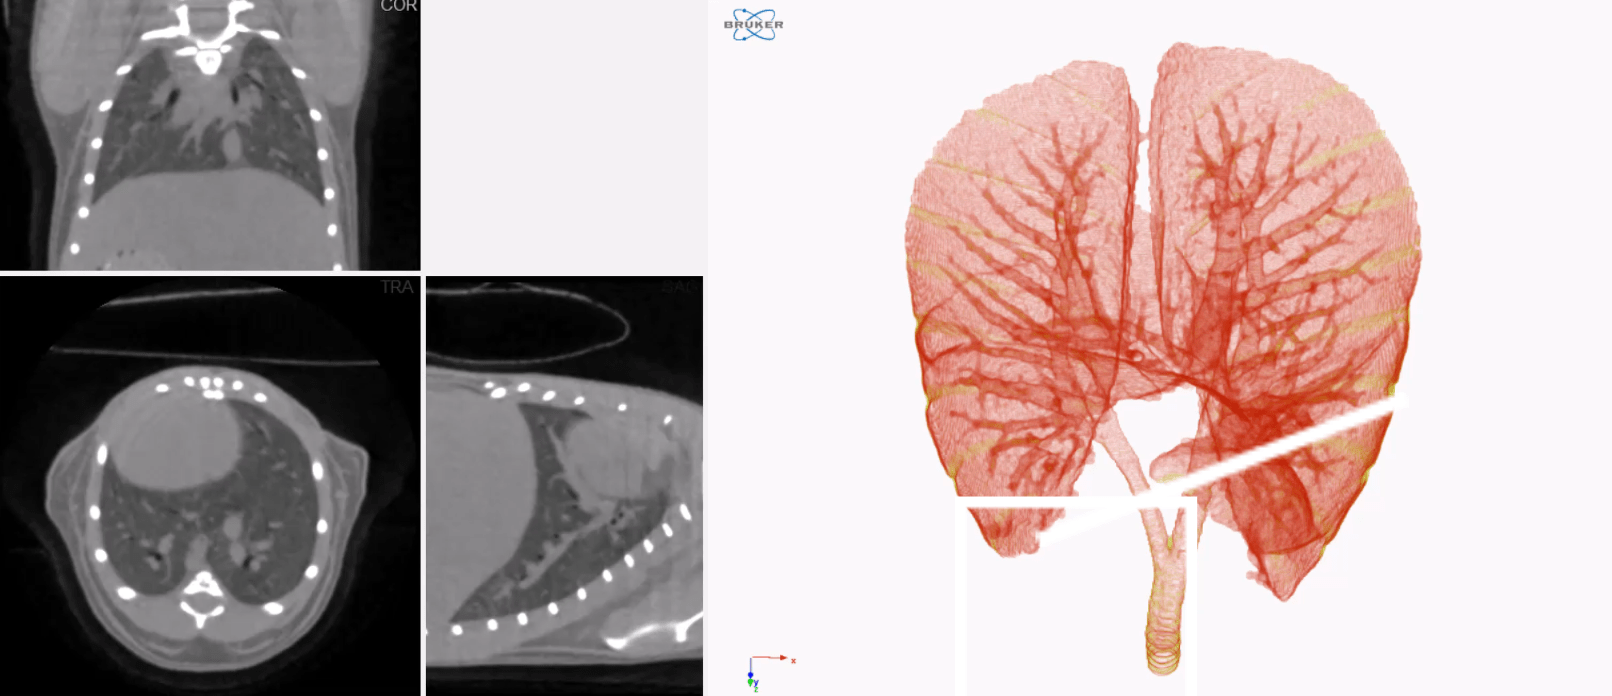

In-vivo time-resolved lung imaging

Calculate the volume of the lungs in living mice during the different phases (bins) of the breathing cycle through LISTMODE reconstruction function in the NRECON software. Use plug-ins in the custom processing of the CTAN Quantitative analysis program to separate the lung from the surrounding tissue without having to custom draw regions-of-interests.